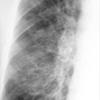

Bronchiectasis

Case 1 PA c/u